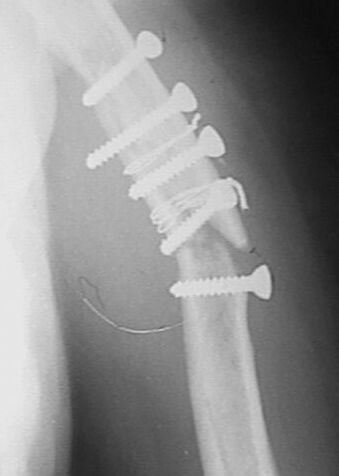

Больная 45 лет оперирована в июле 2002 г, иммобилизация в течение 3 месяцев. После операции были явления неврита лучевого нерва, которые в последующем исчезли. Во время проведения ЛФК отмечается появление болей, патологическая подвижность в месте перелома, деформация плеча.

Проводилась консультация на форуме октябрь 2002, по дальнейшей тактике лечения . Из-за поломки дрелей пришлось ограничиться закрытой репозицией и иммобилизацией торакобрахиальной повязкой в течении 3 мес. Проводили стимуляцию сращения препаратами:"Миокальцикс" и "Ca D3 Никомед" Рентгенконтроль 14.01.03 . Клинически сращение хорошее.Интересно узнать какие препараты используются вами для стимуляции сращения?

Считаю неграмотным вкручивание винтов с конусными или закругленными головками, так как они вклиниваясь в кость, раскалывают ее. Два крайних винта на представленных снимках захватили только по одному из отломков. О